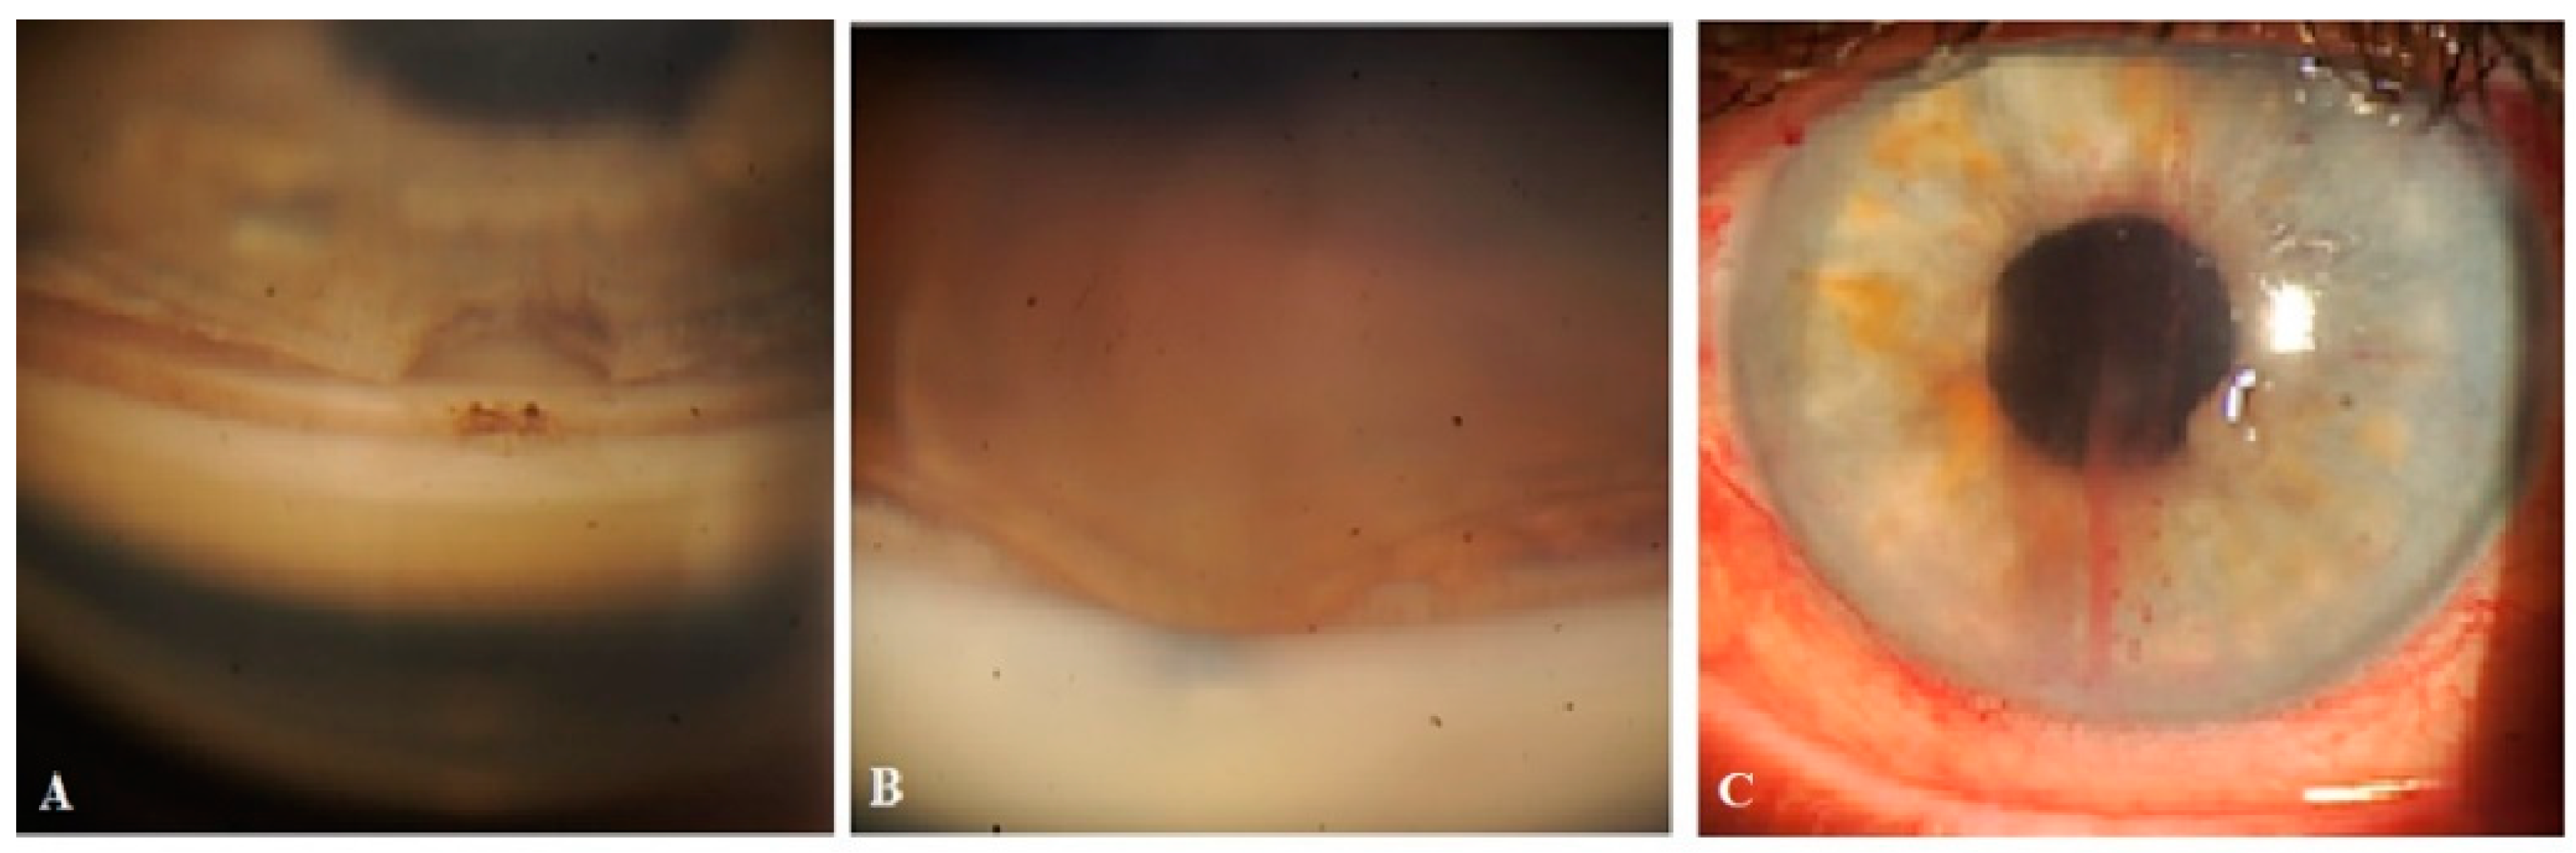

Figure 9.

Slit-lamp view of the surgical site and superior quadrants in a patient’s left eye in which CLVs developed immediately after Nd:YAG laser trabeculotomy: (A) Ten minutes after Nd:YAG laser trabeculotomy, the surgical site and nearby areas are free from CLVs; some swelling at the surgical site persists. (B) Ten minutes after Nd:YAG laser trabeculotomy, another slit-lamp view of the superior temporal quadrant showing a plexus of CLVs (black arrows). (C) Thirty minutes after the procedure, slit-lamp view of the superior temporal quadrant after massaging the area with the lid margin; a well-developed plexus of CLVs can be observed far away from the surgery site. CLV = conjunctival lymphatic vessel; Nd:YAG laser = neodymium yttrium aluminum garnet laser.

Figure 10.

Slit-lamp view of the right eye of a patient in whom CLVs developed without Nd:YAG laser trabeculotomy: (A) Slit-lamp view of the superior temporal quadrant of the eyeball on day 21 after surgery, showing a plexus of CLVs developed far away from the surgery site (arrow with black borders). (B) The same view with a red-free filter. (C) Same site as in (A,B); an Enface image (OCT-angio) demonstrating sausage-shaped lymphatic vessels with uneven calibers (arrows with black borders). CLV = conjunctival lymphatic vessel.